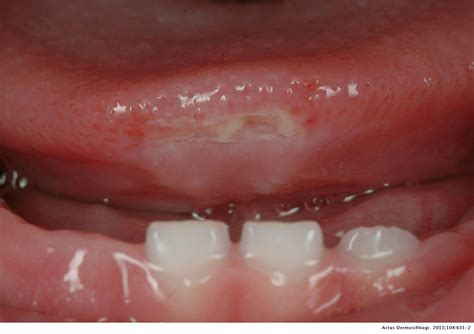

Mouth ulcers, also known as canker sores, are small, painful lesions that develop inside the mouth or at the base of the gums. In infants, these ulcers can appear on the tongue, inside the cheeks, or on the gums. They are typically round or oval with a white or yellow center and a red border. Mouth ulcers in infants can be caused by various factors, including: